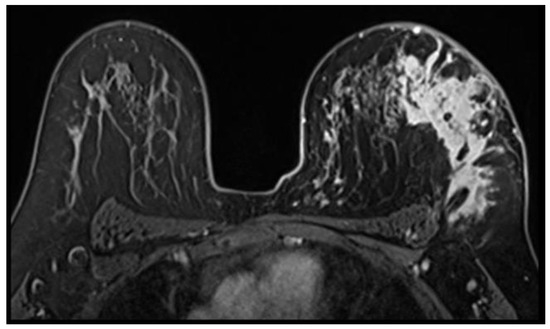

Idiopathic Granulomatous Mastitis